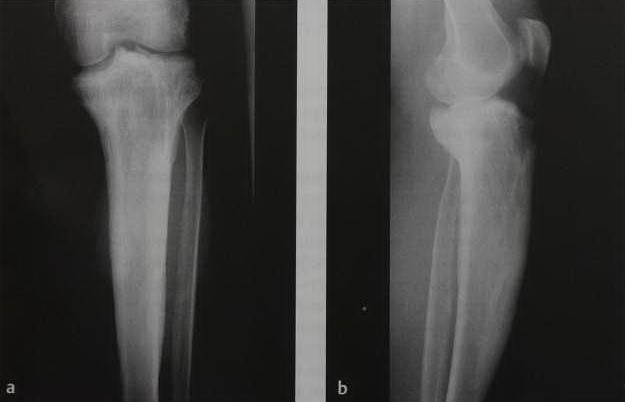

а, b Мужчина 72 лет с болезнью Педжета большеберцовой кости. На рентгенограмме большеберцовой кости в проекциях а) прямой, b) боковой определяется расширение кости, склероз, грубая трабекулярность.